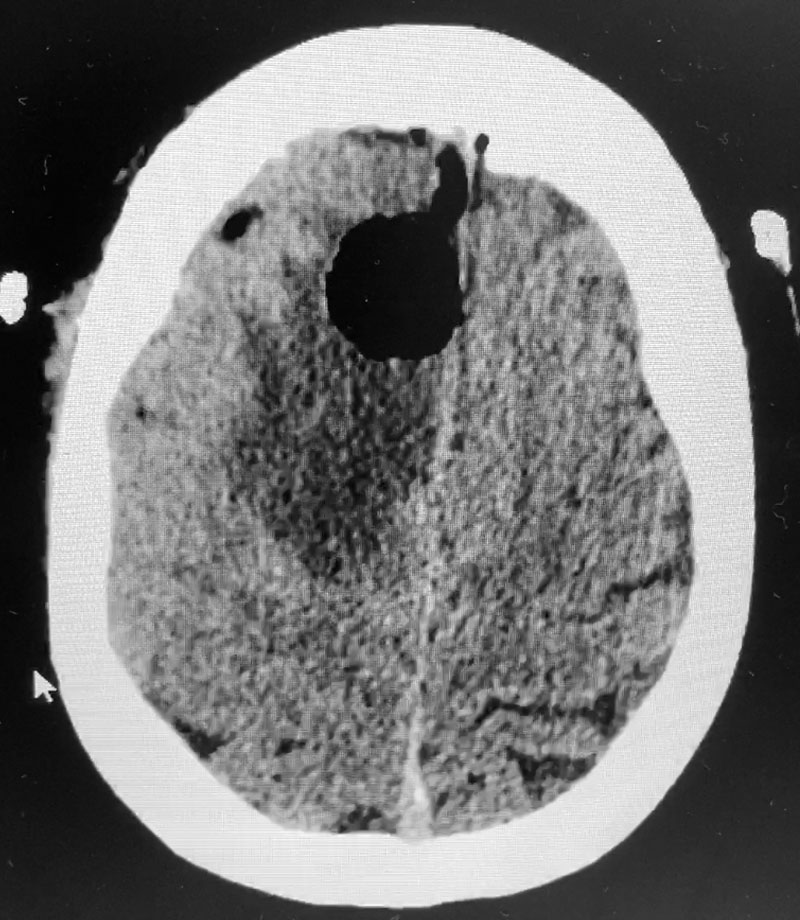

Figure 3: Post operative CT scan.